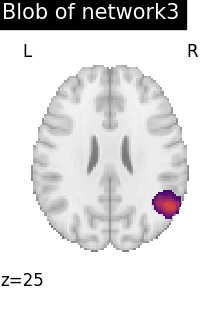

# To reduce the complexity, we choose to display all the regions

# extracted from network 3

regions_indices_network3 = np.where(np.array(extraction.index_) == 3)

for index in regions_indices_network3[0]:

cur_img = index_img(extraction.regions_img_, index)

coords = find_xyz_cut_coords(cur_img)

plotting.plot_stat_map(

cur_img,

display_mode="z",

cut_coords=coords[2:3],

title="Blob of network3",

colorbar=False,

cmap="inferno",

vmax=15,

)